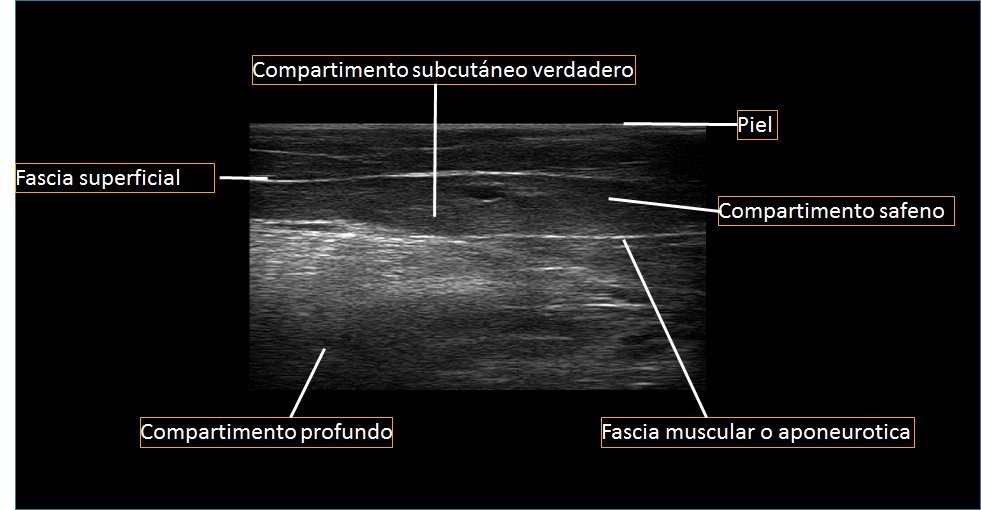

Sistema venoso superficial. Está formado por la vena safena mayor (término que reemplaza a “safena interna”) y la vena safena menor (llamada antes “safena externa”). Ambas transcurren por la pierna y el muslo en el compartimento safena, limitado por la fascia superficial hacia la parte anterior y la fascia muscular hacia la posterior (1, 2, 3) (Fig. 1).